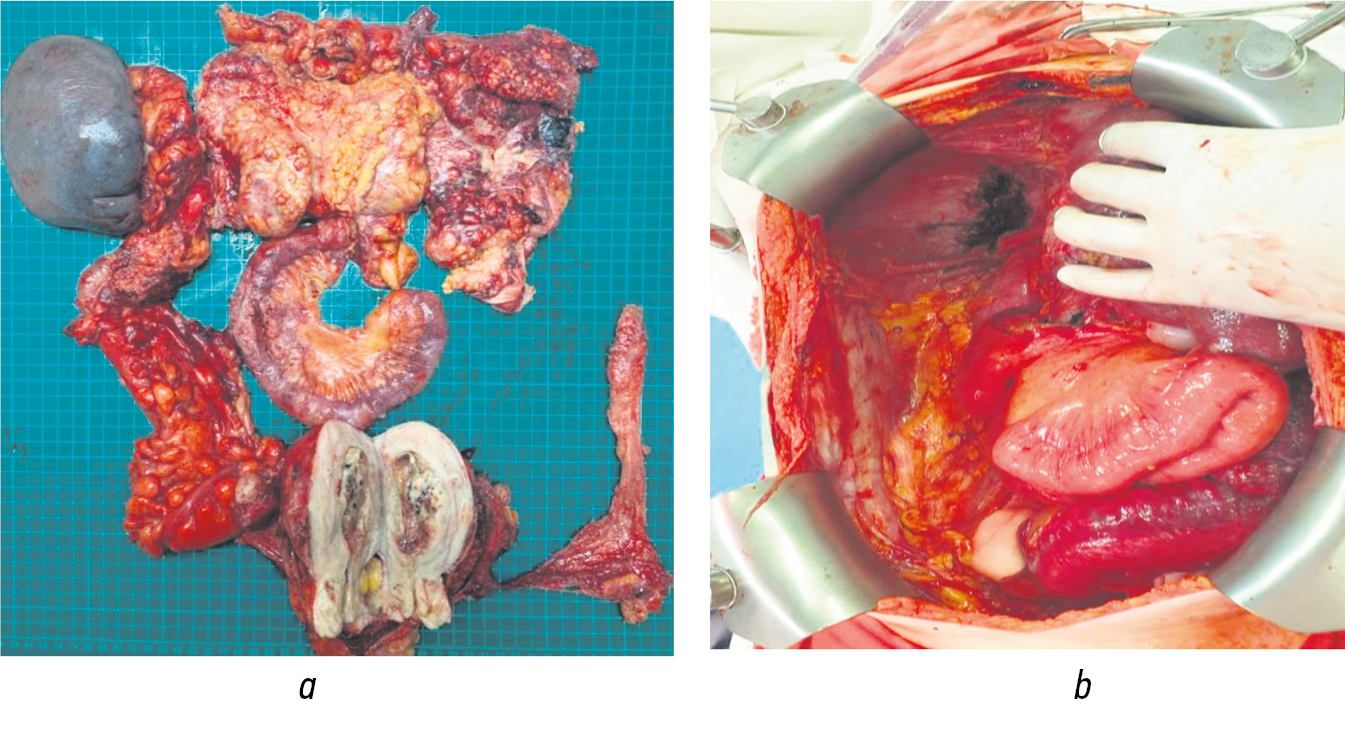

В основе циторедуктивной хирургии у больных обеих групп лежали различные варианты мультивисцеральных резекций, перитонэктомия, а также лимфодиссекция (табл. 6, рис. 2).

Рис. 2. Циторедуктивное оперативное вмешательство. Органокомплекс, удаленный в результате мультивисцеральной резекции (а). Вид операционного поля после завершения циторедуктивного вмешательства и перитонэтомии (b)

При этом необходимо обратить внимание на достоверно большую частоту выполнения перитонэктомии и лимфодиссекции при двухэтапных циторедуктивных оперативных вмешательствах (см. табл. 6). По всей видимости, двухэтапная тактика обеспечила благоприятные условия для выполнения полного объема оперативного вмешательства, необходимого для полноценной санации организма от опухолевой ткани (рис. 3).

Рис. 3. Вид операционного поля после выполнения перитонэктомии левого верхнего квадранта живота, спленэктомии и атипичной резекции левой доли печени (а). Аортоподвздошная бифуркационная и тазовая билатеральная лимфодиссекция у больной диссеминированным раком яичника, осложненным некрозом (b)